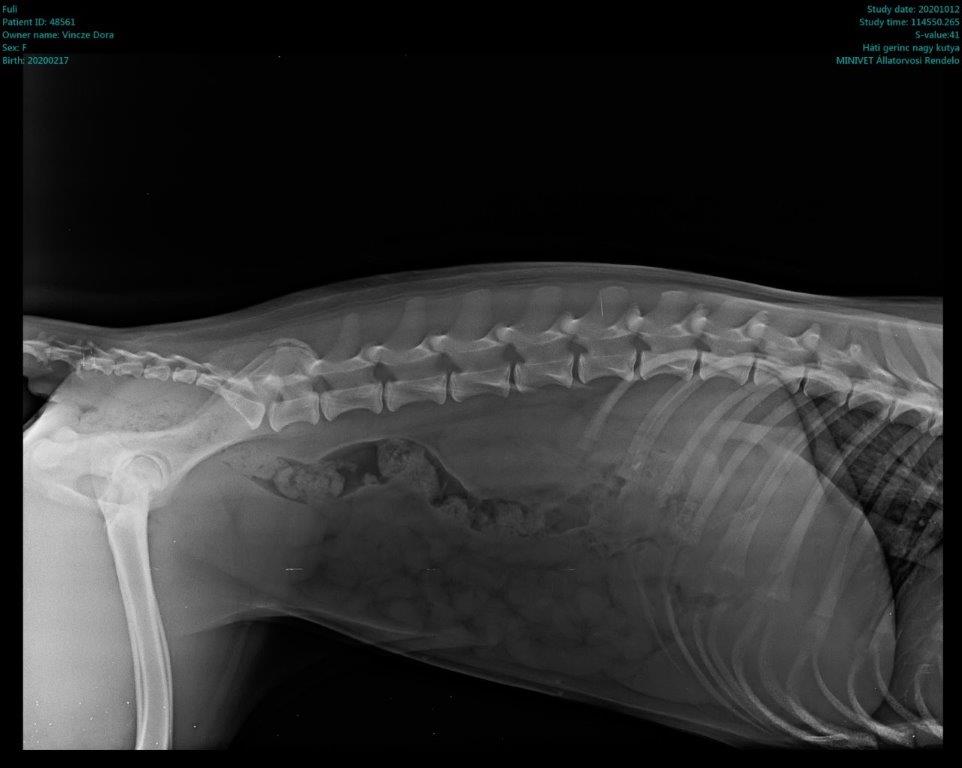

Füli kutyusunk egy jelenleg kb másfél éves, mentett, bántalmazott keverék, szuka kutyus (15 kg-os, vékony testalkatú, közepes magasságú, rövidszőrű keverék kutyus). Sérülése egy korábbi bántalmazásból eredt, mikor kiskutyaként husánggal úgy megverhették, hogy combnyaktörése lett. Ezt mi derítettük ki, mikor hozzánk került tavaly októberben. Akkor észrevettük, hogy aggasztóan sántít, és elvittük megröntgeneztetni. Több orvos véleményét is kikértem, és mindannyian azt tanácsolták, hogy műttessük meg (elég drasztikus műtéttel, a combcsontfej egy részét kivágták volna).

Molnár doktor úr egyedüliként, a röntgen kép alapján, arra bíztatott, hogy mivel a kutyus még növekedésének vége előtt állt, próbáljunk ki egy 3 hónapos csont- és porcépítő csomagot. Így is tettünk. Már kezdetben is nagy javulást észleltünk. Pár hét után el-elmaradozott a sántítás és szép lassan teljesen elmúlt. De természetesen nem elégedtünk meg ennyivel. Májusban az ivartalanítási műtét során kértem az orvost, hogy készítsen röntgenfelvételt Füli lábáról. A röntgen el is készült, és nagy örömünkre, már ez az állatorvos is azt mondta, hogy nincs szükség a combcsontfej műtétjére.